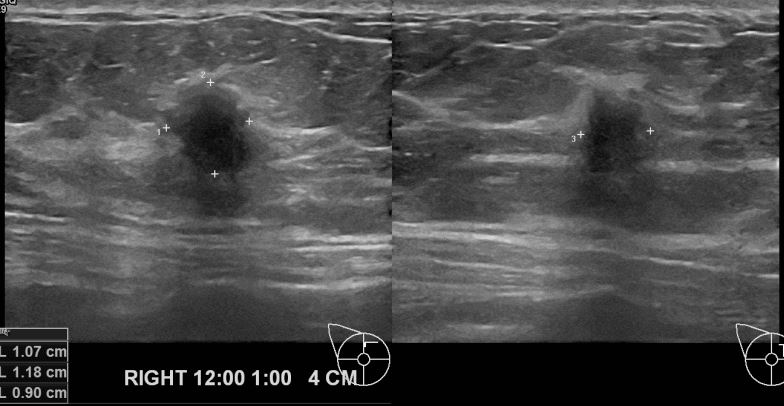

건강검진상 이상소견 내원하신 40대 여성분으로 초음파검사이후  우측 유방 조직검사 진행후 유방암 진단되셨읍니다. 빠른쾌유 바랍니다